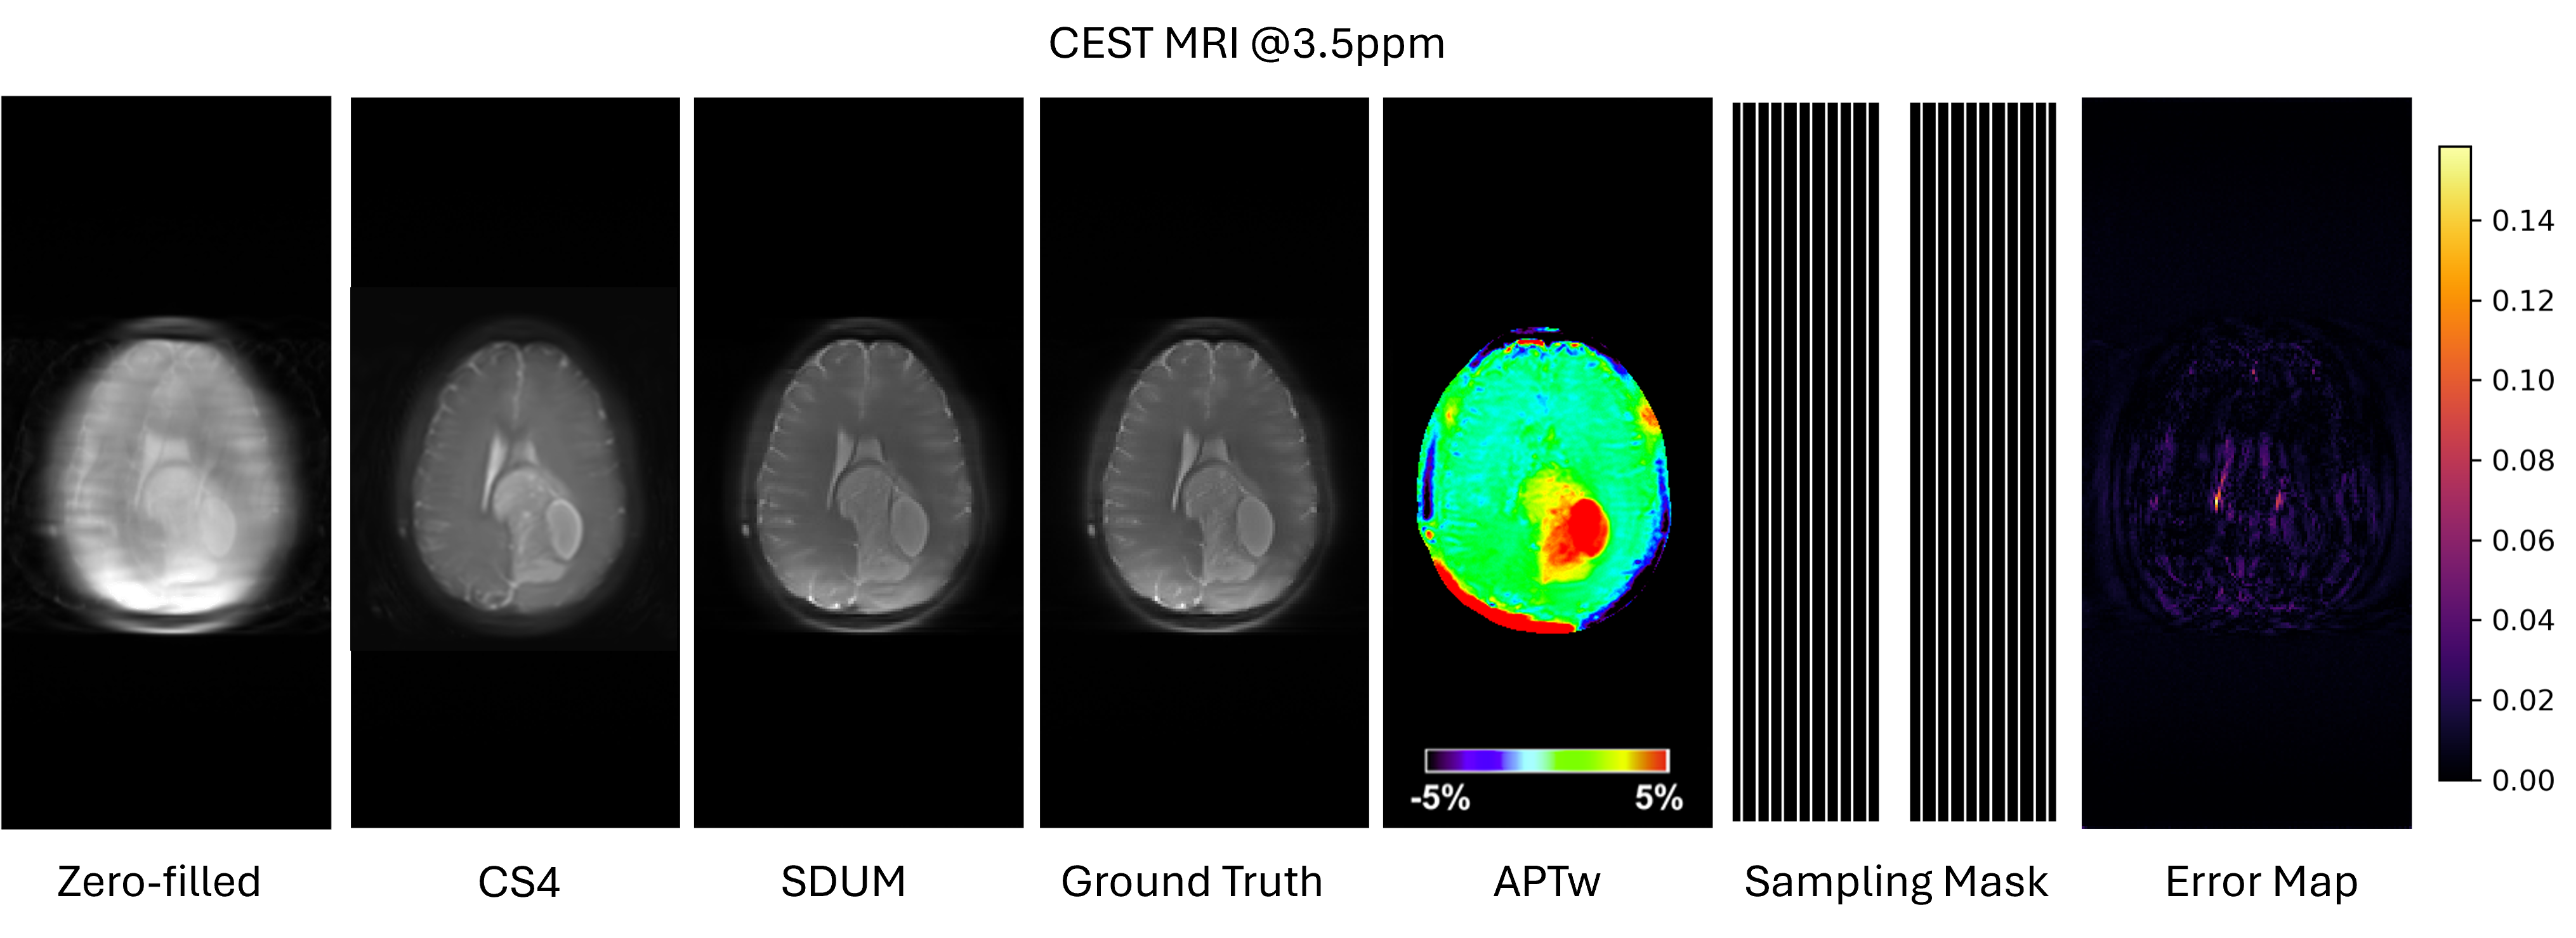

Figure 7: Zero-shot CEST MRI reconstruction on in-house data. From left to right: zero-filled reconstruction from the 4×4\times undersampled multi-coil k-space, CS4 reconstruction from the scanner using the Philips commercial compressed sensing algorithm, SDUM, fully sampled reference, the derived amide proton transfer–weighted (APTw) map at ±\pm 3.5 ppm, the corresponding one-dimensional Cartesian sampling mask, and the per-pixel absolute error map between SDUM and the reference (values in the range [0,0.14][0,0.14]). SDUM produces an image that is visually indistinguishable from the fully sampled reference and substantially reduces residual aliasing compared with CS4, achieving PSNR =43.57=43.57 dB and SSIM =0.9769=0.9769 without any fine-tuning on this dataset.

Chemical Exchange Saturation Transfer (CEST) MRI scans were performed on an in-house brain dataset using a 3T scanner (Achieva, Philips Medical Systems, Best, the Netherlands) of patients with brain tumor. The body coil was used for excitation, and signal reception employed a 32-channel phased-array head coil (Invivo, Gainesville, FL). The CEST protocol used a saturation field strength B1B_{1} of 2μT2\,\mu\text{T} applied for 2 s, repetition time TR=6.5\mathrm{TR}=6.5 s, echo time TE=8.31\mathrm{TE}=8.31 ms, and slice thickness of 4 mm. Fully sampled multi-coil k-space data were acquired together with data retrospectively undersampled by a factor of four using Cartesian phase-encoding undersampling. The figure shows the magnitude image and APTw map at the 3.5 ppm saturation offset, where CEST contrast manifests as subtle percent-level signal changes that are highly sensitive to reconstruction errors.

The Philips scanner, CEST pulse sequence, and image contrast were not present in the training data for SDUM, so this experiment constitutes a strict zero-shot test on an unseen vendor and protocol. As illustrated in Fig. 7, SDUM removes the strong aliasing artifacts visible in the zero-filled reconstruction and recovers finer structures and lesion contrast that are still degraded in the CS4 baseline, which corresponds to the vendor-provided Philips commercial compressed sensing reconstruction from the scanner. Quantitatively, SDUM attains 43.57 dB PSNR and 0.9769 SSIM with respect to the fully sampled reference, while preserving the fidelity of the downstream APTw map. This demonstrates that our foundation model can generalize across scanners and pulse sequences and can support quantitative CEST imaging in a zero-shot fashion.